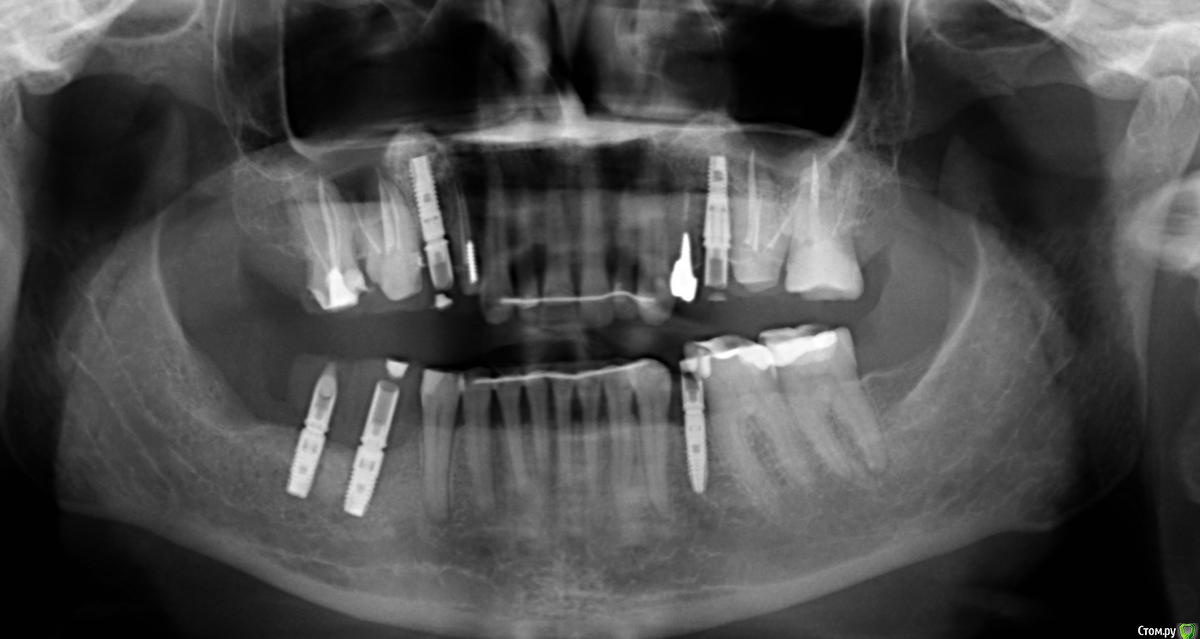

Глеб Митрофанов Опубликовано 12 сентября, 2015 Поделиться Опубликовано 12 сентября, 2015 (изменено) Направлена ортопедом , к которому пришла от другого хирурга и ортопеда , которые оперировали и изготавливали времянки соответственно . Пришла с просьбой - хочу сосочки ! Изменено 12 сентября, 2015 пользователем Глеб Митрофанов Ссылка на комментарий

Глеб Митрофанов Опубликовано 12 сентября, 2015 Автор Поделиться Опубликовано 12 сентября, 2015 А какой вопрос? С какой целью написали?Что возможно сделать , чтоб сделать максимально приближенное к желаемому ? Работа с мягкими тканями , времянками ?? Ссылка на комментарий

faity Опубликовано 12 сентября, 2015 Поделиться Опубликовано 12 сентября, 2015 пластика с бугров наверху, снизу полностью переделывать ортопедию и делать пластику с бугров. Гамборена вчера показывал как))) carlos показывает уже год 4 Ссылка на комментарий

Aquarius Опубликовано 12 сентября, 2015 Поделиться Опубликовано 12 сентября, 2015 Что возможно сделать , чтоб сделать максимально приближенное к желаемому ? Работа с мягкими тканями , времянками ??Если имплант не глушить, то по моему никак Ссылка на комментарий

Глеб Митрофанов Опубликовано 12 сентября, 2015 Автор Поделиться Опубликовано 12 сентября, 2015 Если имплант не глушить, то....Первая мысль , которая пришла в голову , заглушить винты Ссылка на комментарий

колесников Опубликовано 12 сентября, 2015 Поделиться Опубликовано 12 сентября, 2015 а кто сказал что будет легко?)Поддерживаю. Ортопедию с нуля Ссылка на комментарий

Глеб Митрофанов Опубликовано 12 сентября, 2015 Автор Поделиться Опубликовано 12 сентября, 2015 Поддерживаю. Ортопедию с нуляТак и будет , ветку Carlosa посмотрел насчет хирургии Ссылка на комментарий

Mane Опубликовано 12 сентября, 2015 Поделиться Опубликовано 12 сентября, 2015 снимаешь временную коронкупересаживаешь сст с бугра на тонкий формировательждешь месяцоцениваешьпротезируешь 2 Ссылка на комментарий